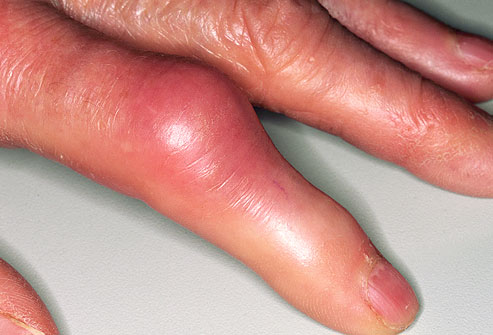

痛风的症状之手指

尿酸在手指肿沉积便可累及手指。在痛风发作时注意不要过多活动以缓解疼痛。